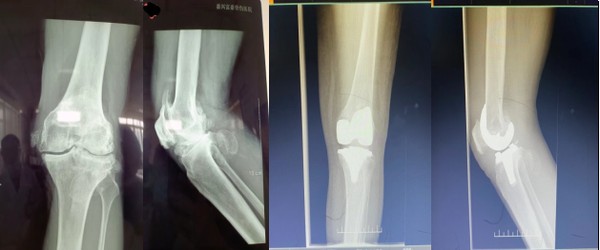

日前,我院骨一科成功为两名膝关节重度骨性关节炎患者实施了人工膝关节置换术。

据骨一科甘德军主任介绍,两例患者膝关节重度骨性关节炎多年,采取保守治疗方式效果不佳,近期膝关节疼痛加重,已影响到正常行走,给生活造成了极大的不便。患者住院后,骨科组织全科医生会诊对病人的病情进行认真分析和讨论,结合医院设施和业务技术水平及手术经验,客观评估手术风险,最后决定在保证万无一失的前提下,夏百红副主任主刀对病人实施膝关节置换术。患者术后三天逐渐下地行走,手术效果良好。

该项手术的成功实施,填补了我县在人工膝关节置换领域的空白,实现了我县独立完成人工膝关节置换术零的突破。近年来我院不断加强医院重点学科建设,提高医疗服务能力,使百姓在家门口就可以享受到优质医疗服务,大大减轻了病人外出就医负担,使得百姓不出县就可看好病。